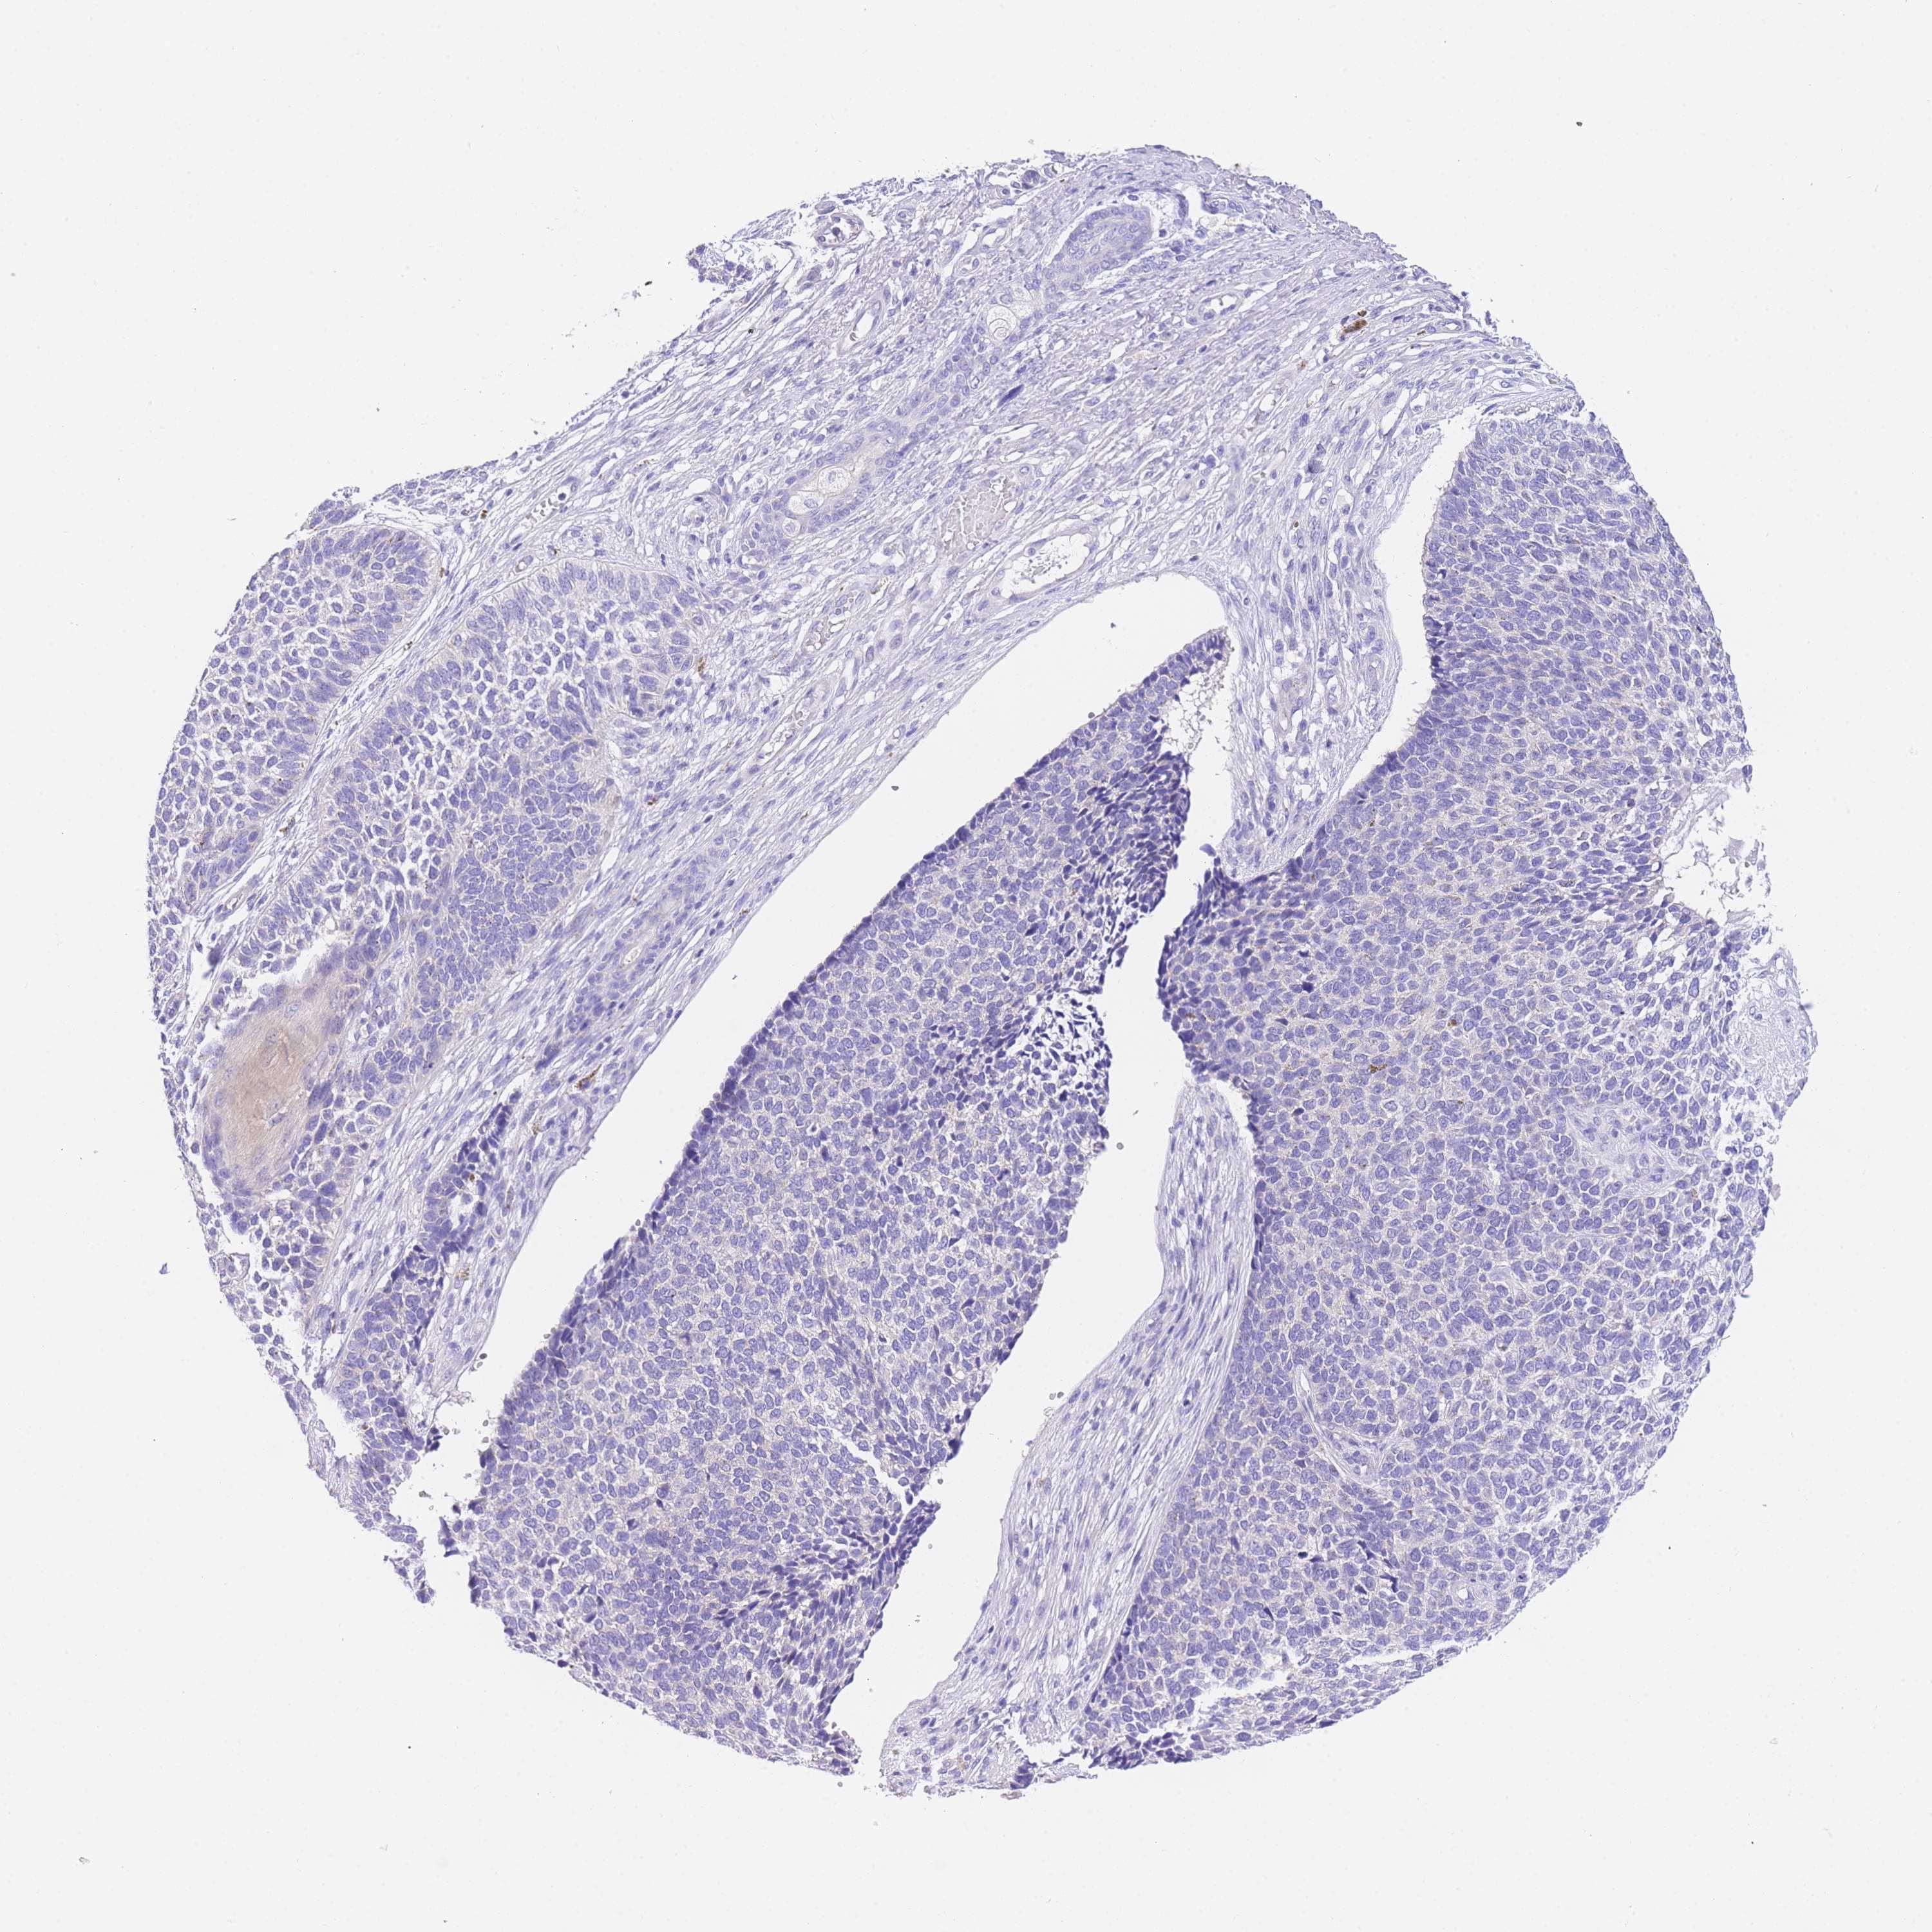

Basal cell and squamous cell cancer

SKIN CANCER - Protein expressioni

A mouse-over function shows sample information and annotation data. Click on an image to view it in a full screen mode. Samples can be filtered based on level of antibody staining by selecting one or several of the following categories: high, medium, low and not detected. The assay and annotation is described here.

Each image is clickable and will lead to virtual microscopy that enables deeper exploration of all samples and also displays staining intensity scores, fraction scores and subcellular localization as well as patient and tissue information for each sample.

Antibody HPA049809

Basal cell carcinoma

Squamous cell carcinoma, NOS

Squamous cell carcinoma, metastatic, NOS